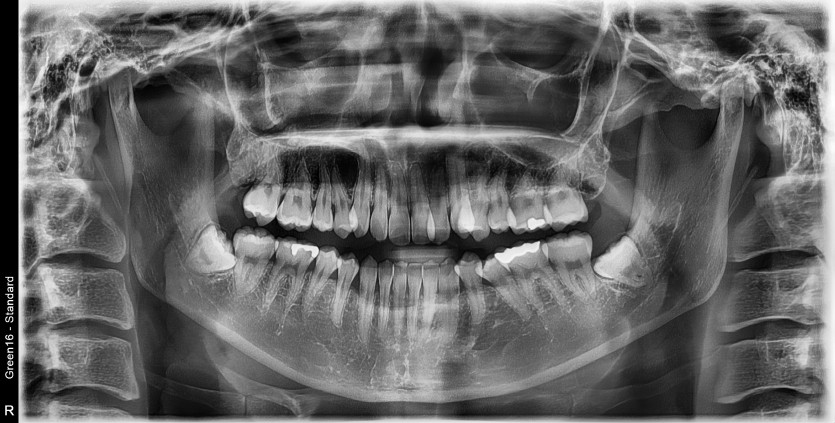

#38,48 사랑니 발치

구강 외과 전문의가 당일 발치했습니다.